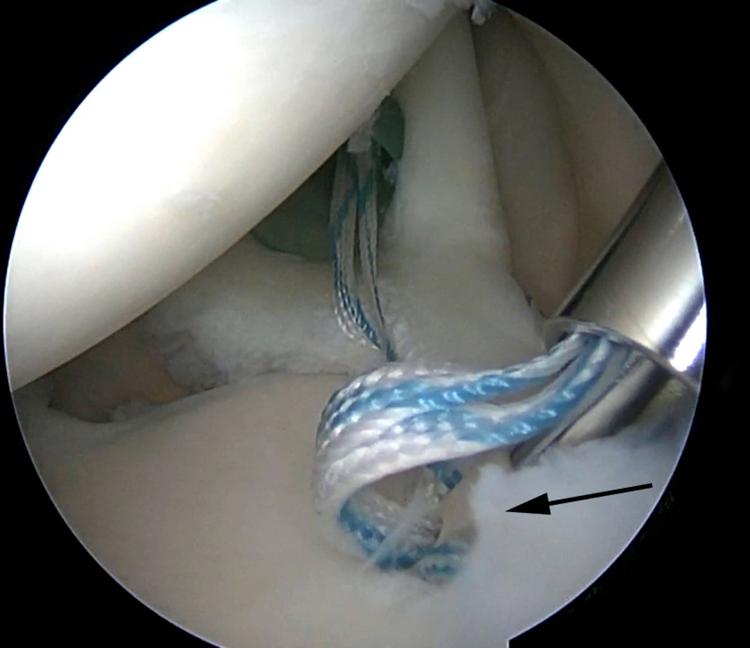

SLAP tears have been a controversial topic in shoulder surgery for decades. The indications for repair of SLAP tears, as well as the methods of repair, have undergone a recent evolution. The use of intra-articular knots for SLAP repair has fallen out of favor because of potential abrasive damage to the rotator cuff and glenohumeral articular cartilage due to knot migration and prominence. In response to this potential iatrogenic injury, arthroscopic techniques have undergone an evolution using advanced techniques with low-profile knotless repairs. We describe our preferred low-profile knotless technique for SLAP repair using LabralTape (Arthrex) in a horizontal mattress configuration.

几十年来,肩袖上盂唇(SLAP)损伤一直是肩部手术中颇具争议的话题。SLAP损伤的修复指征以及修复方法最近都有所发展。由于结的迁移和突出可能对肩袖和肱盂关节软骨造成潜在的磨损损伤,关节内打结用于SLAP修复已不再受青睐。针对这种潜在的医源性损伤,关节镜技术已发展为采用先进技术进行低轮廓无结修复。我们描述了一种使用LabralTape(Arthrex)以水平褥式缝合方式进行SLAP修复的首选低轮廓无结技术。